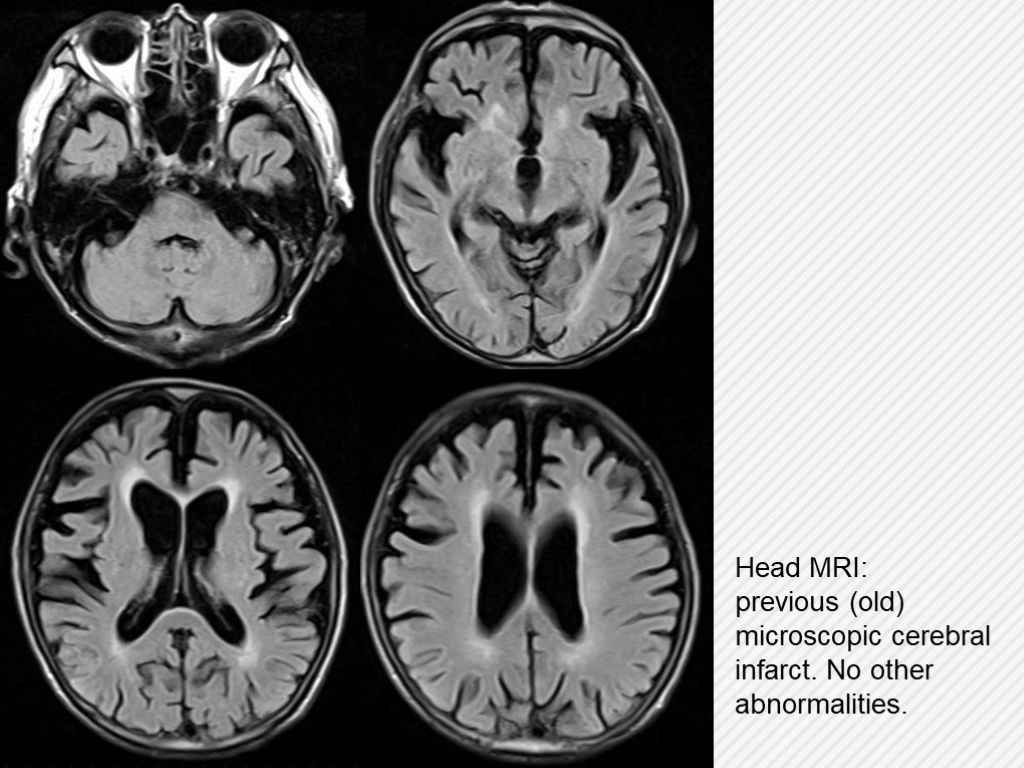

Head MRI: previous (old) microscopic cerebral infarct. No other abnormalities.